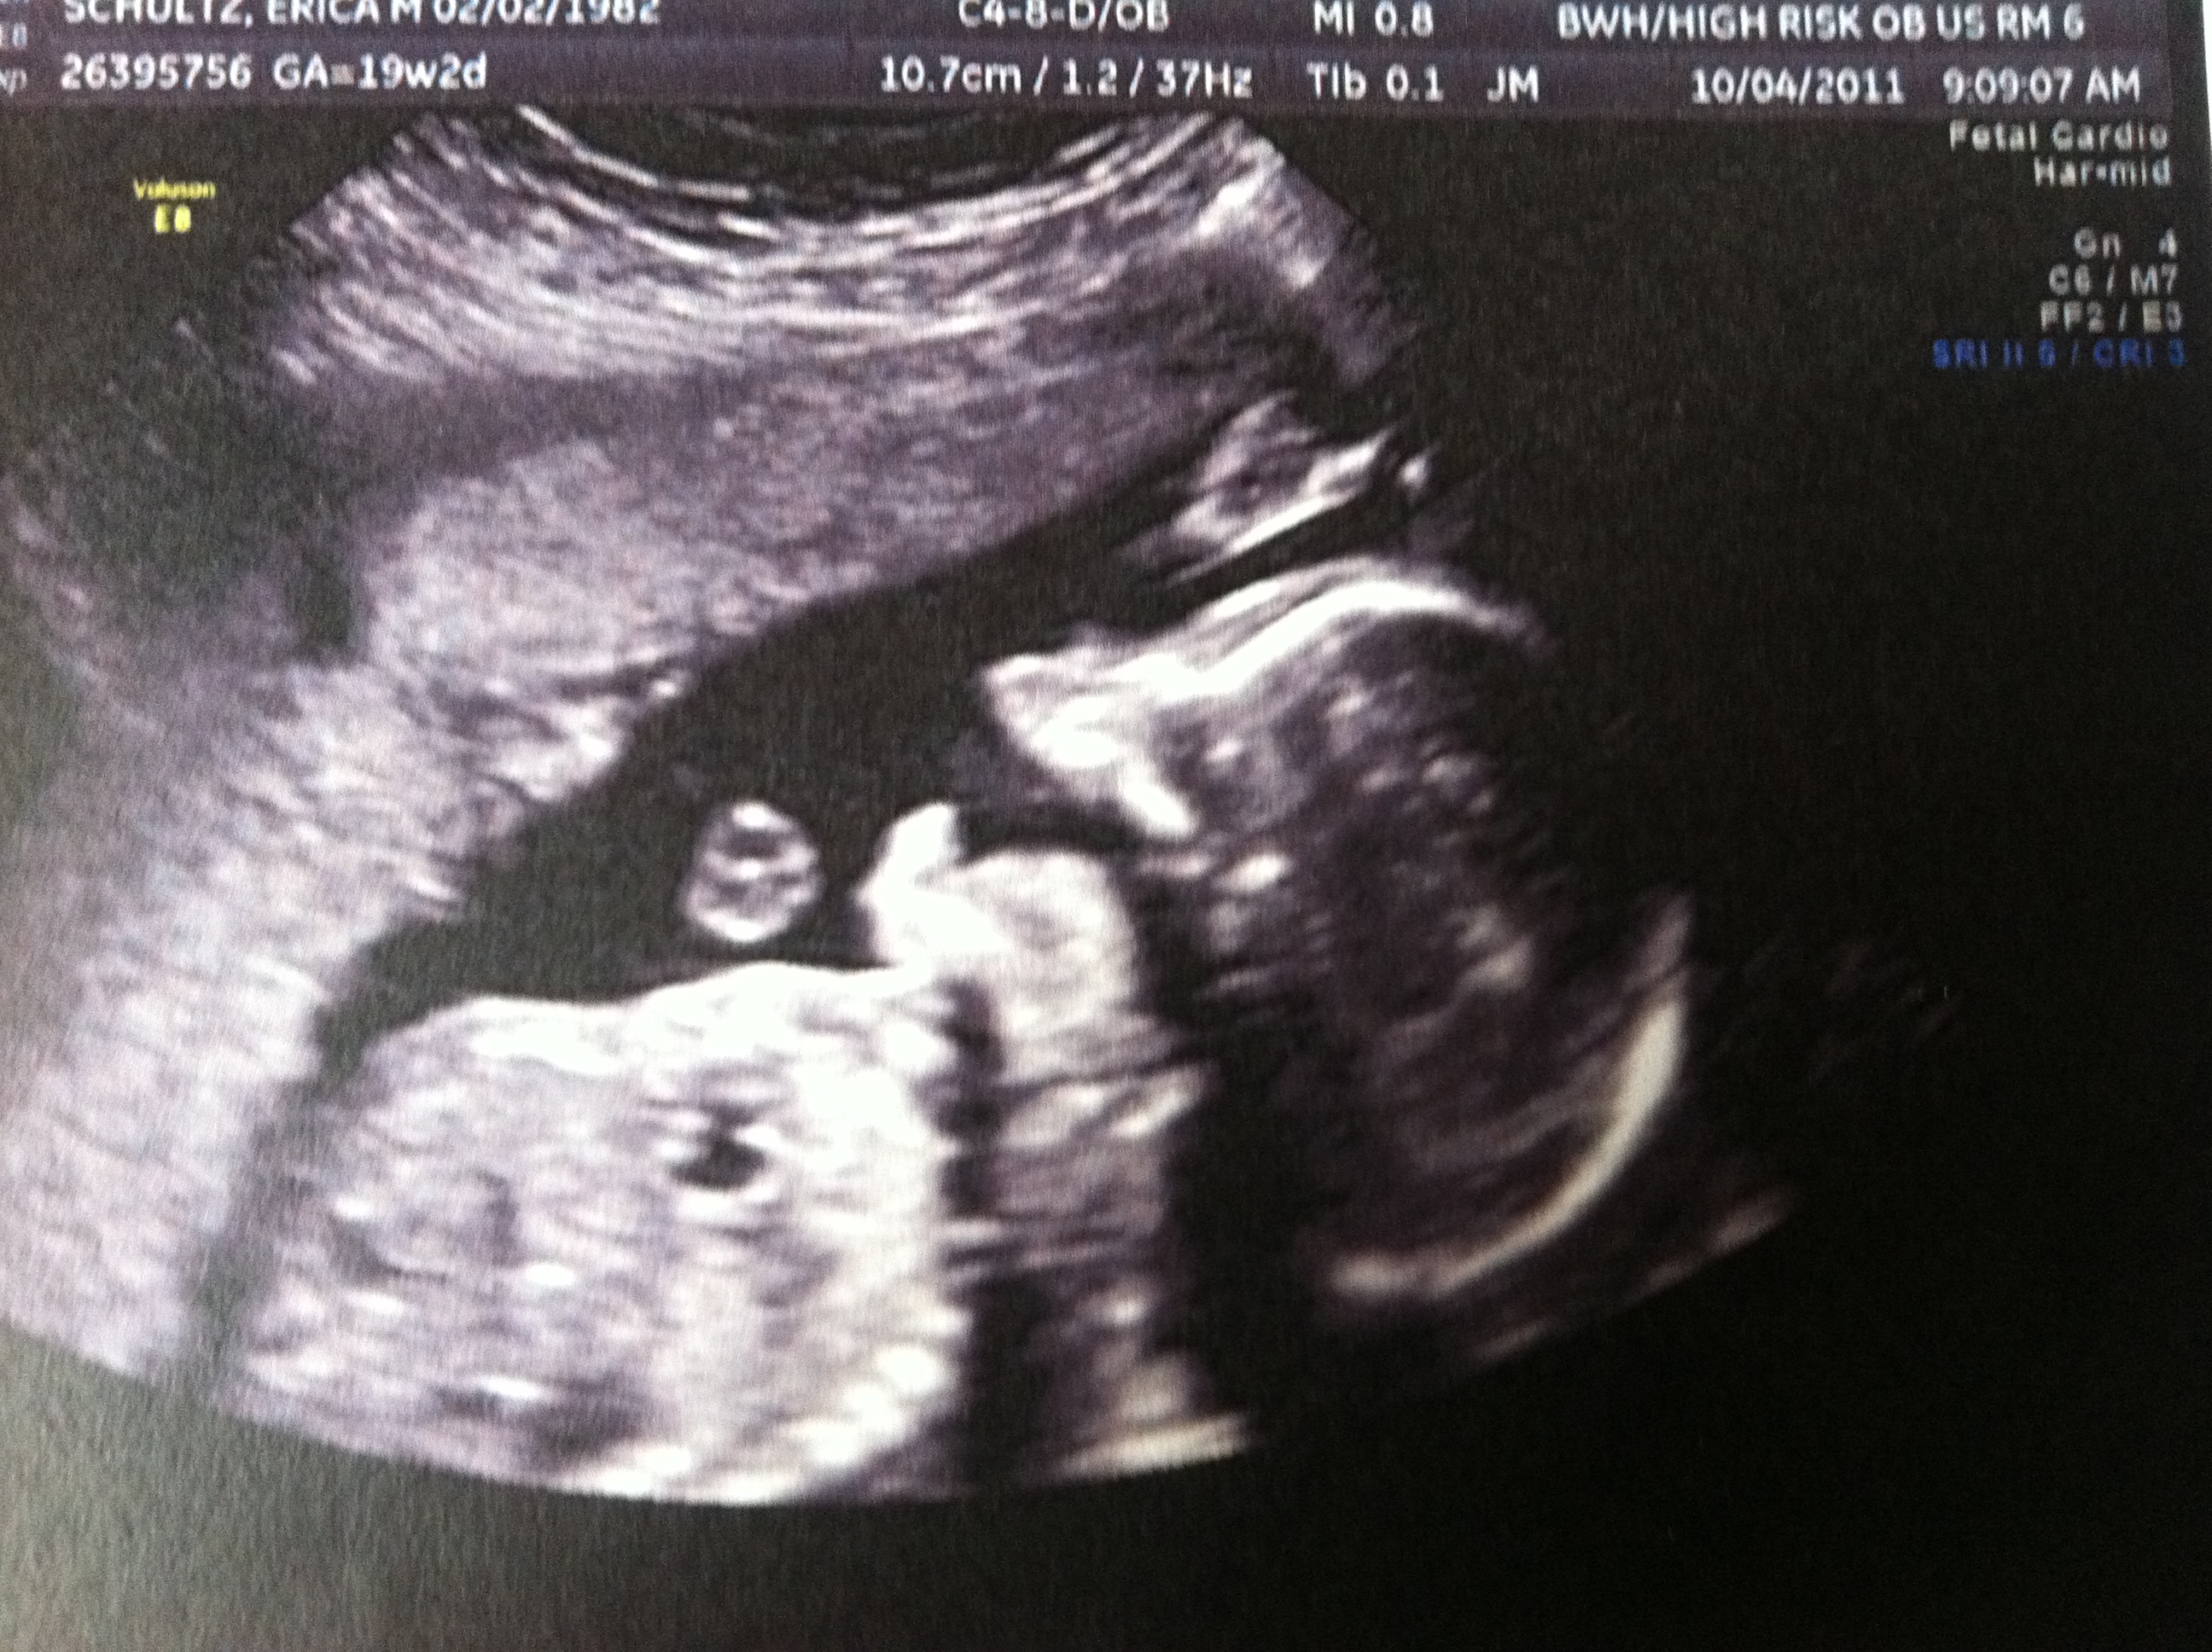

I have a big mouth just like my father.